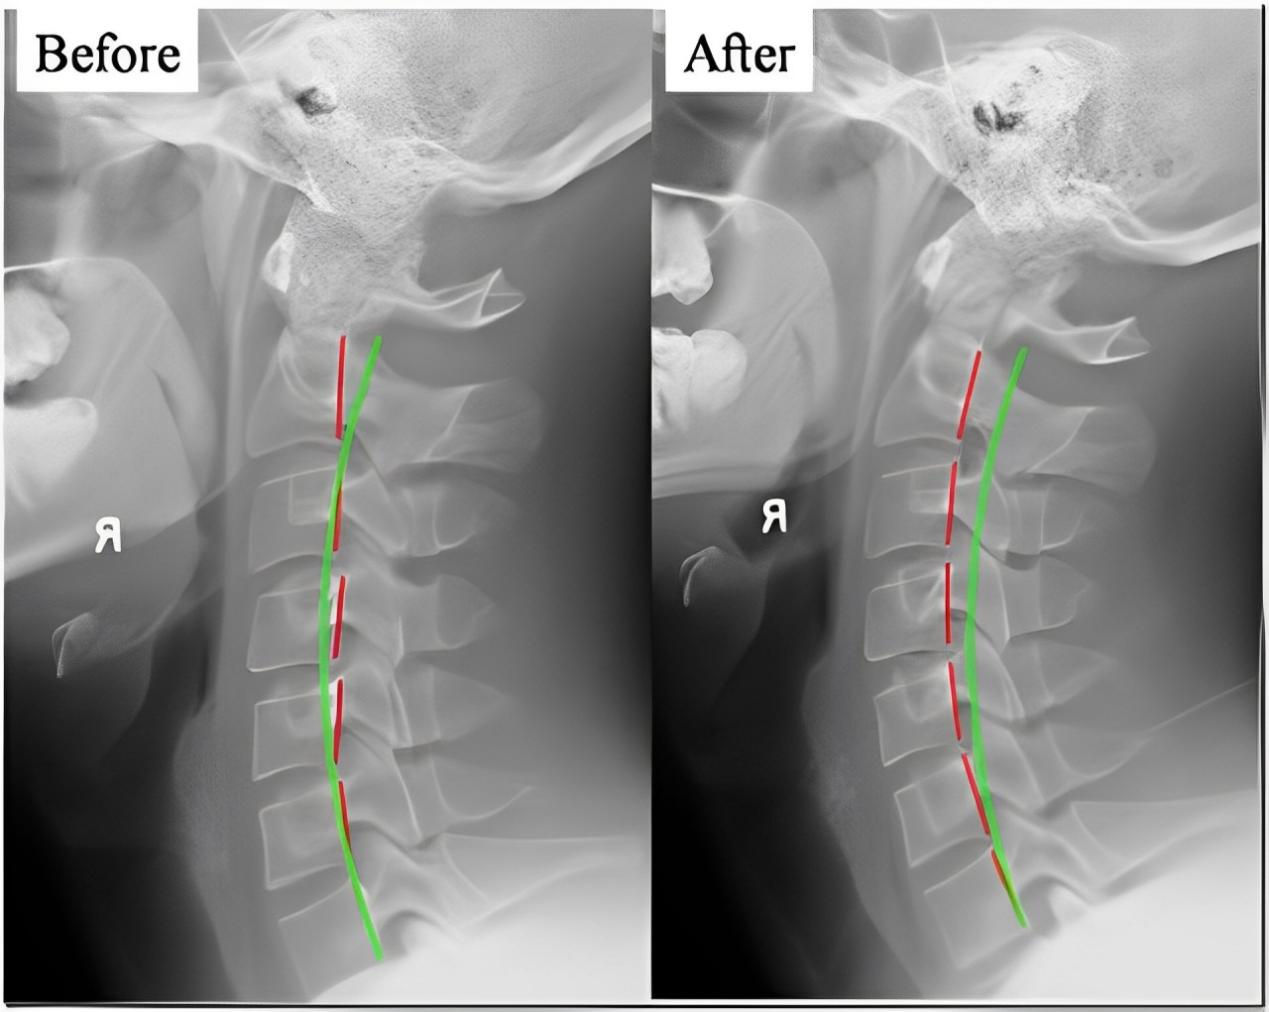

四、 恢復脊椎自然曲度

五、矯正完和矯正后的對比案例: